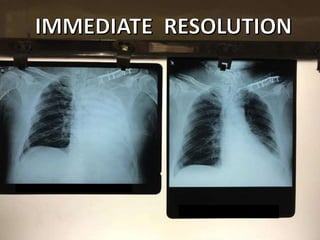

A patient presented with a penetrating chest injury, showing clinical signs of a hemothorax or hemopneumothorax including cyanosis, decreased or absent breath sounds on the affected side, tracheal deviation away from the affected side, dull percussion notes, unequal chest rise, tachycardia, hypotension, and pale, cool, clammy skin. An ultrasound and chest X-ray confirmed a hemothorax or hemopneumothorax, which was treated with insertion of an intercostal drain and assisted ventilation if necessary.